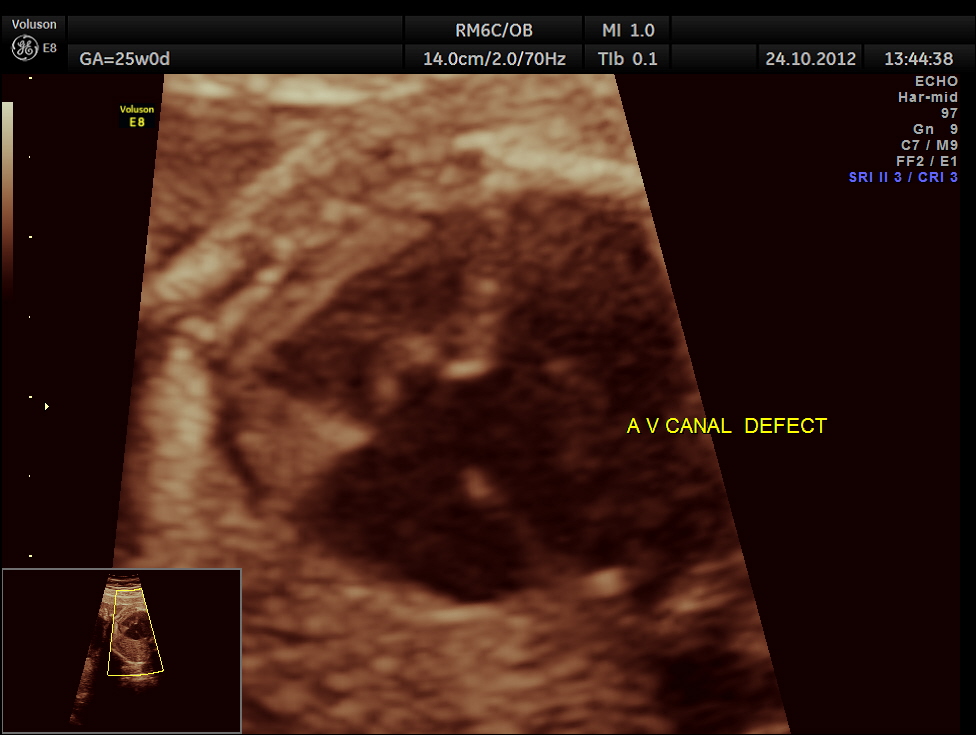

The scan was done around 25 weeks of gestation :

colour flow clearly demonstrating the atrio ventricular septal defect